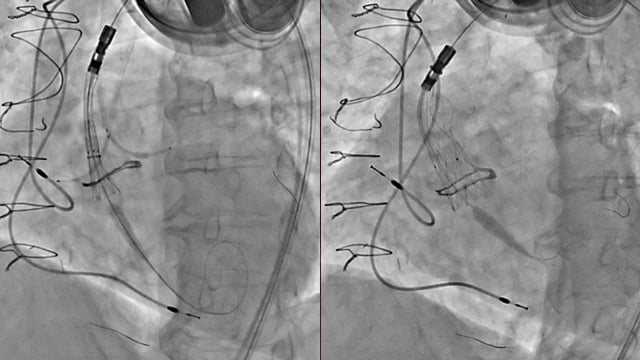

TTVR - Part 2

17 Nov 2025 – From PCR London Valves 2025

This session presents advances in transcatheter tricuspid valve replacement (TTVR), highlighting cases such as Evoque valve implantation post-cardioband, TTVR following valve annuloplasty in amyloidosis, rescue interventions after edge-to-edge repair failure, and management of complex anatomical challenges including left inferior vena cava and lead interference in high-risk...